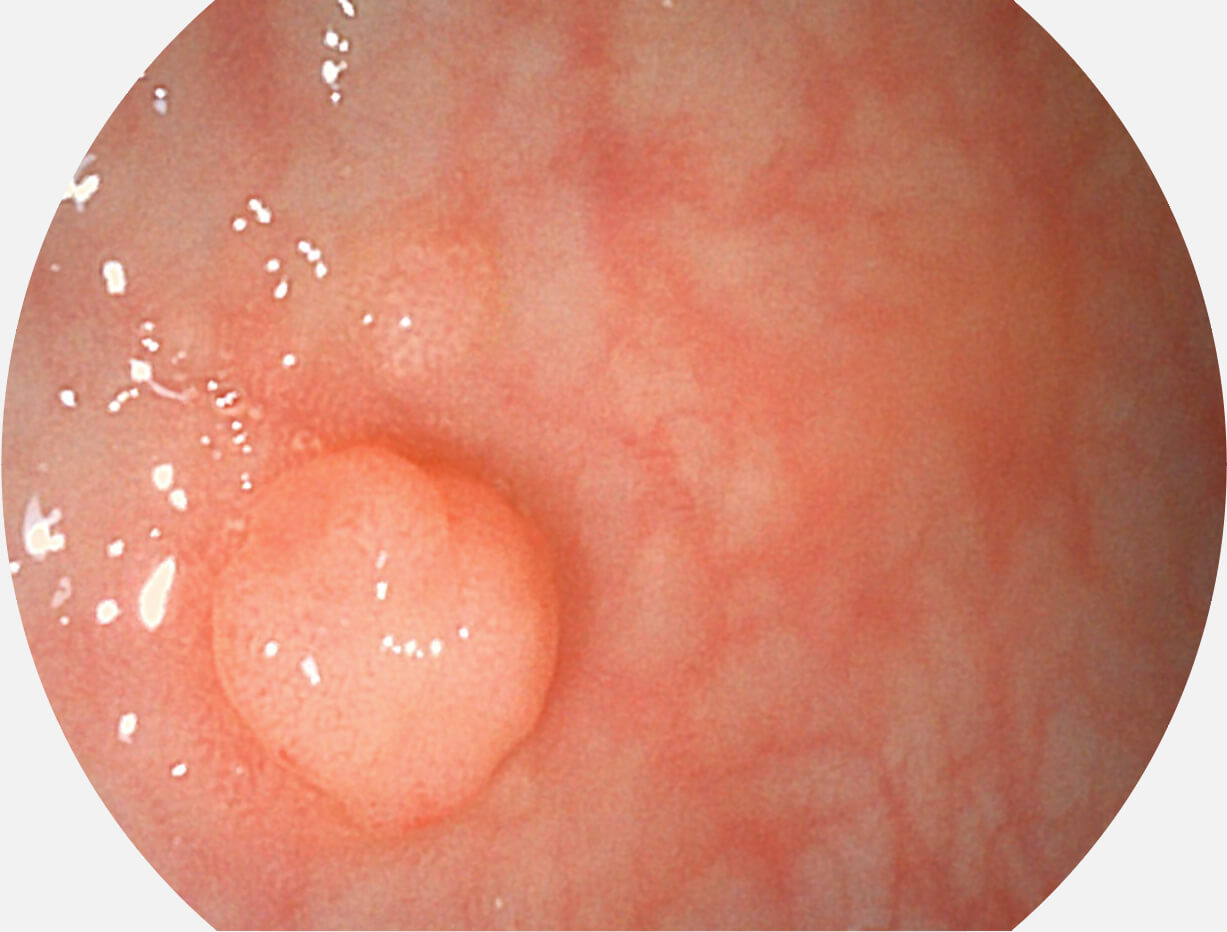

图像具有高亮度、高黏膜血管颜色对比度的特点,且不改变粘液、食物残渣、粪便的基本颜色,可在中远景下进行观察,助力消化道早期疾病的诊断。

白光图像